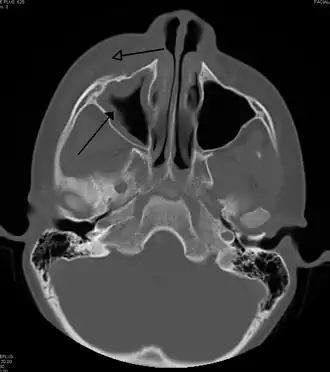

Периорбитальный целлюлит, вызванный стоматологической инфекцией (которая также приводит к верхнечелюстному синуситу))

Периорбитальный целлюлит, также известный как пресептальный целлюлит (но не следует путать с орбитальным целлюлитом, находящимся за перегородкой), — воспаление и заражение века и части кожи вокруг глаз[1] впереди орбитальной перегородки. Может быть вызван повреждением кожи вокруг глаз, и последующим распространением на веко; заражением носовых пазух вокруг носа (синусит); или распространением инфекции в другие места через кровь.

Периорбитальный целлюлит необходимо дифференцировать от орбитального целлюлита, который является чрезвычайной ситуацией и требует внутривенного введения (IV) антибиотиков. В отличие от орбитального целлюлита, у пациентов с периорбитальным целлюлитом отсутствуют выпуклые глаза (экзофтальм), ограниченное движение глаз (офтальмоплегия), боль при движении глаз, или потеря зрения. Если какой-либо из этих признаков присутствует, надо полагать, что пациент имеет орбитальный целлюлит и начать лечение IV антибиотиками. КТ-сканирование может быть сделано, чтобы очертить расширение инфекции.